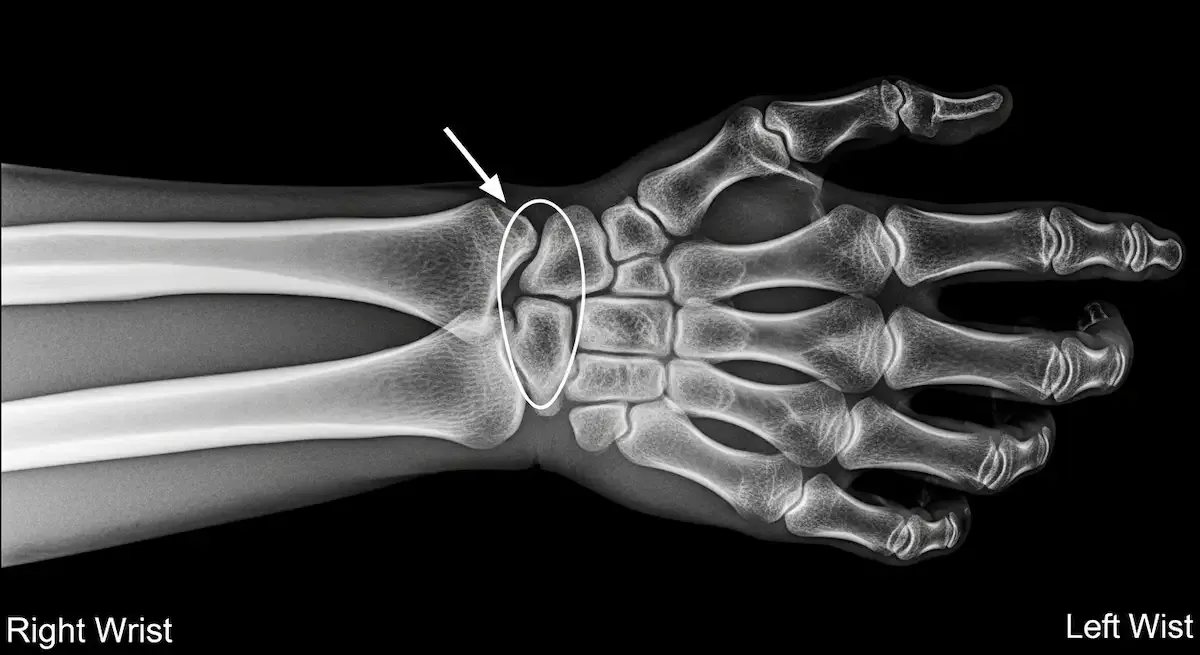

A Síndrome do Canal de Guyon é uma neuropatia compressiva do nervo ulnar no punho. O canal é formado por ossos do carpo e ligamentos, conduzindo o nervo e a artéria ulnar até a mão.

Quando existe estreitamento, cisto, edema ou sobrecarga mecânica, o nervo perde condução, surgindo alteração de sensibilidade e déficit motor dos músculos intrínsecos.

Fraturas, artrose do carpo, cistos sinoviais e tumores benignos também estreitam o canal.

O diagnóstico da Síndrome do Canal de Guyon começa pela história clínica e exame físico com testes de provocação e digitopercussão sobre o canal.

- A ultrassonografia detecta espessamento do nervo e pesquisa cistos.

- Radiografias avaliam fraturas e artrose.